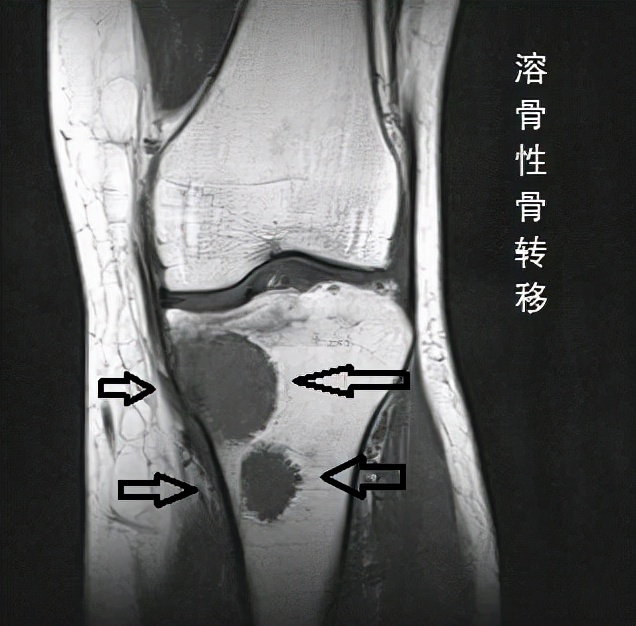

And in this case, multiple bone metastases.